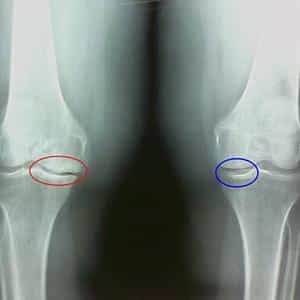

Для диагностики артрита и артроза используются клинические обследования, рентгенография, МРТ и анализы крови. Врач может оценить состояние суставов, выявить воспалительные маркеры и определить степень повреждения хрящевой ткани.

Артроз развивается постепенно и на ранних стадиях может быть незаметен. Его часто путают с обычной физической усталостью. Хроническую форму артроза также называют остеоартрозом. На вопрос, что хуже – артроз или остеоартроз, ответ очевиден. Остеоартроз является следствием прогрессирования артроза и его более тяжелой формой.